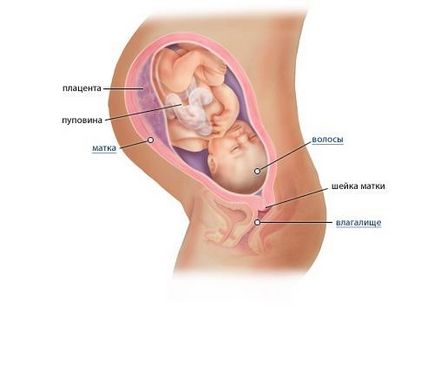

Ha az orvos írja: „35 hetes, farfekvéses bemutatása”, az azt jelenti, hogy a születés természetes nem lesz lehetséges. Ismerje meg, hogyan a gyümölcsöt kell helyezni a 35 terhességi hét.

Ebben az időszakban nagyon fontos, mert a baba kerül a méhbe. Ha a kártya van írva: „35 hetes terhesség, farfekvéses bemutatása”, azaz, persze, ez nem ok az aggodalomra. De fel kell készülni, amit valószínűleg kénytelenek császármetszést. A gyerek már nagyon nagy, és a ritka esetekben, amikor ez a kifejezés, hogy képes dobni a fejjel lefelé. A természetes ródium farfekvéses, hogy amikor a baba „ül” a has, hogy a pápa, és a lába alján vannak, ez nagyon veszélyes mind az anya és a baba.

A gyümölcsöt a 35. terhességi hét továbbra is késlelteti a zsírszövet. Shoulders kerekítve gyerek és megpuhult. A szőrzet, amely beburkolta a testét, a gyermek, az úgynevezett lanugo gyakorlatilag eltűnt ebben az időben. A hozzávetőleges súlya a magzat két és fél kilogramm a 35. héten, és a növekedés közeledik negyven centiméter.

Egyre nehezebb megbirkózni álmatlanság éjjel. A magzat nyomást gyakorol a húgyhólyag és a várandós anya már többször az éjszaka folyamán futtatni a WC-vel.

Most a gyerek megy egy másik szakaszában a fejlődés: ez héttel később a fejét beesik a medence és azonnal enyhíti a hangulat. Lesz fellélegezhetnek, és már nem folytatja a folyamatos fájdalom a bordák alatt. Másrészt, ez ismét okoz szívdobogást, beleértve az éjszakai vizelés. Mert most a gyermek kezdődik, hogy gyakoroljon nyomást a húgyhólyag. Azonban meg kell jegyezni, hogy vannak olyan esetek, amikor a baba, és nem megy fel a születés, ez is az egyik fajta a norma.

Egészében véve, minden rendszerek és szervek már elég fejlett, és nagyon hajlandó önállóan dolgozni. Ugyanakkor, még mindig lehetősége van arra, hogy javítsa, ami mi történik az utolsó időszak a terhesség. Gyümölcs súlya 35 hetes terhesség körülbelül 2,8 kg és a magassága 47 cm, vagy még egy kicsit.